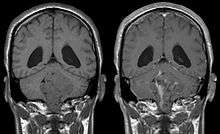

Ependymomas make up about 5% of adult intracranial gliomas and up to 10% of childhood tumors of the central nervous system (CNS). Their occurrence seems to peak at age 5 years and then again at age 35. They develop from cells that line both the hollow cavities of the brain and the canal containing the spinal cord, but they usually arise from the floor of the fourth ventricle, situated in the lower back portion of the brain, where they may produce headache, nausea and vomiting by obstructing the flow of cerebrospinal fluid. This obstruction may also cause hydrocephalus. They may also arise in the spinal cord, conus medularis and supratentorial locations.[4] Other symptoms can include (but are not limited to): loss of appetite, difficulty sleeping, temporary inability to distinguish colors, uncontrollable twitching, seeing vertical or horizontal lines when in bright light, and temporary memory loss. It should be remembered that these symptoms also are prevalent in many other illnesses not associated with ependymoma.

About 10% of ependymomas are benign myxopapillary ependymoma (MPE). MPE is a localized and slowly growing, low-grade tumor. Although some ependymomas are of a more anaplastic and malignant type, most of them are not anaplastic. Well-differentiated ependymomas are usually treated with surgery. For other ependymomas, total surgical removal is the preferred treatment in addition to radiation therapy. The malignant (anaplastic) varieties of this tumor, malignant ependymoma and the ependymoblastoma, are treated similarly to medulloblastoma but the prognosis is much less favorable. Malignant ependymomas may be treated with a combination of radiation therapy and chemotherapy. Ependymoblastomas, which occur in infants and children younger than 5 years of age, may spread through the cerebrospinal fluid and usually require radiation therapy. The subependymoma, a variant of the ependymoma, is apt to arise in the fourth ventricle but may occur in the septum pellucidum and the cervical spinal cord. It usually affects people over 40 years of age and more often affects men than women.